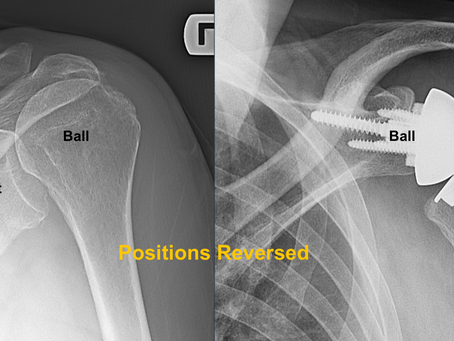

Reverse Shoulder Replacement

Persistent shoulder pain and weakness can severely limit daily activities. Reverse Shoulder Arthroplasty is a modern surgical solution designed for patients with rotator cuff tear arthropathy, complex fractures, or failed shoulder surgeries, offering reliable pain relief and improved shoulder function.